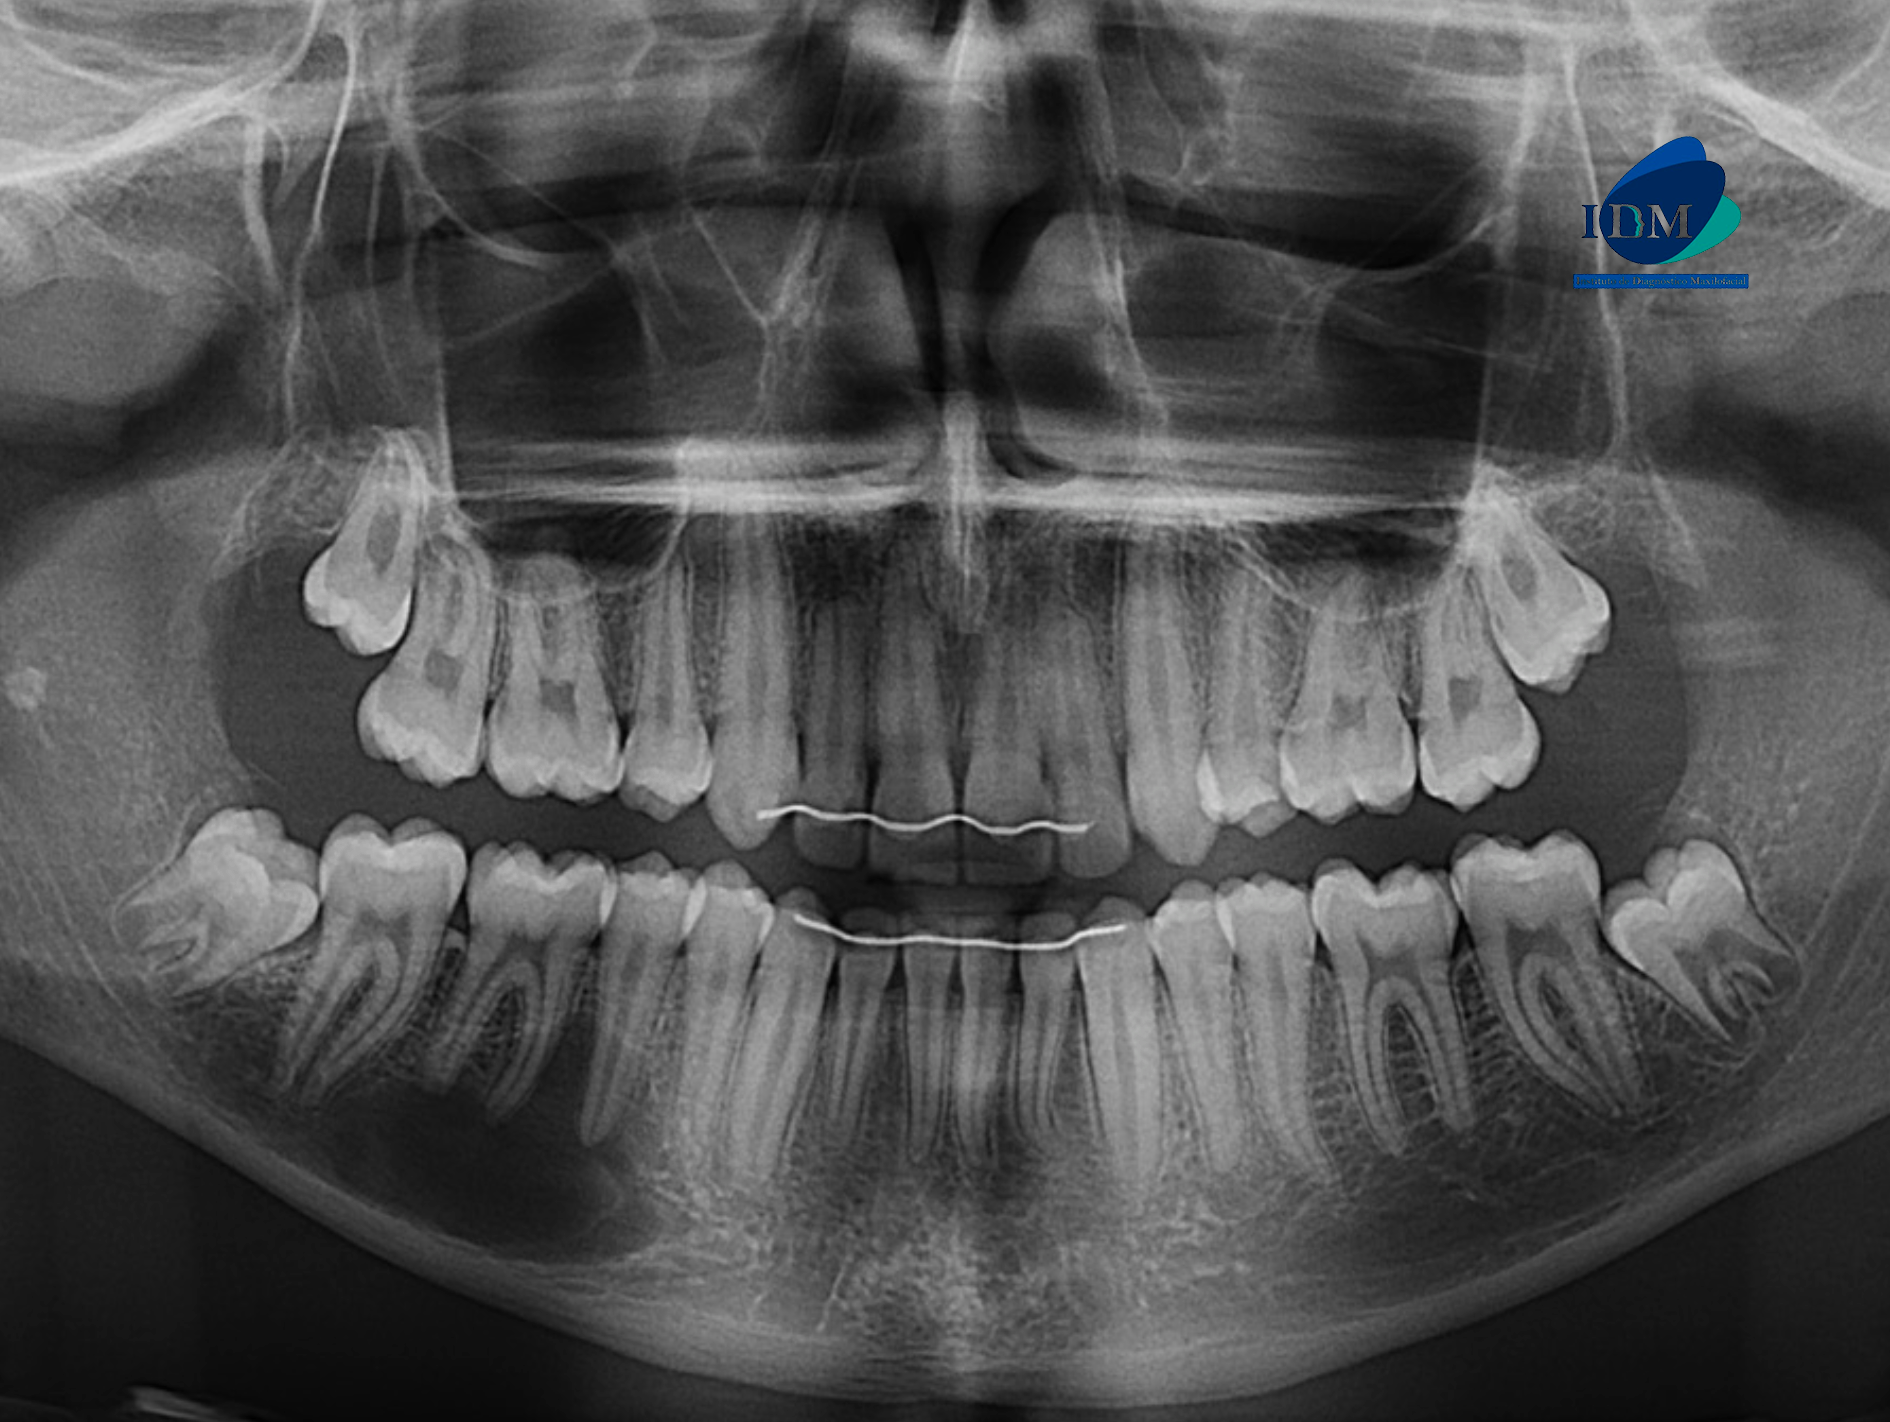

En la radiografía panorámica (Figura 1), se aprecia imagen radiolúcida proyectada en cuerpo mandibular derecho, de limites definidos, bordes parcial mente corticalizados y forma irregular.

Radiografia Panorámica

A la evaluación de la tomografía volumétrica (CBCT) en los cortes axiales (Figura 2) y transaxiales (Figura 3), se aprecia imagen isodensa de limites definidos, que se extiende en sentido cefálico caudal desde tercio medio radicular de pieza 46 hasta borde basal mandibular, en sentido mesio distal desde mesial de pieza 45 hasta apical de pieza 47, que ocasiona desplazamiento del conducto dentario inferior hacia caudal y borramiento parcial de la cortical superior de la misma, adelgazamiento de tabla ósea lingual.